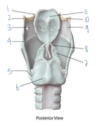

Which structure is labeled by #5?

What is its action?

Cricothyroid muscle

Phonation - Tilts the thyroid forward to tense the vocal cords -> higher pitches

Innervated by the external laryngeal nerve

Which structure is labeled by #7?

Cricothyroid ligament

Which structure is labeled by #7?

Cricoid cartilage

(Also #9)

Which muscle abducts the vocal cords to open the airway?

5 - posterior cricoarytenoid

Which structure is labeled by #3?

Lateral cricoarytenoid muscles

(Adduct/close the vocal cords)

Which structure is labeled by #5?

What is its action?

Posterior cricoarytenoid muscle

Abducts vocal cords -> opens airway

Which structure is labeled by #6?

What is its action?

Recurrent laryngeal nerve

- Motor innervation to laryngeal muscles except cricothyroid muscle

- Visceral sensory below vocal cords

(Internal laryngeal nerve is visceral sensory above vocal cords, external laryngeal is motor to the cricothyroid muscle)

Which fold is labeled by #2?

Vestibular fold (aka false vocal fold)